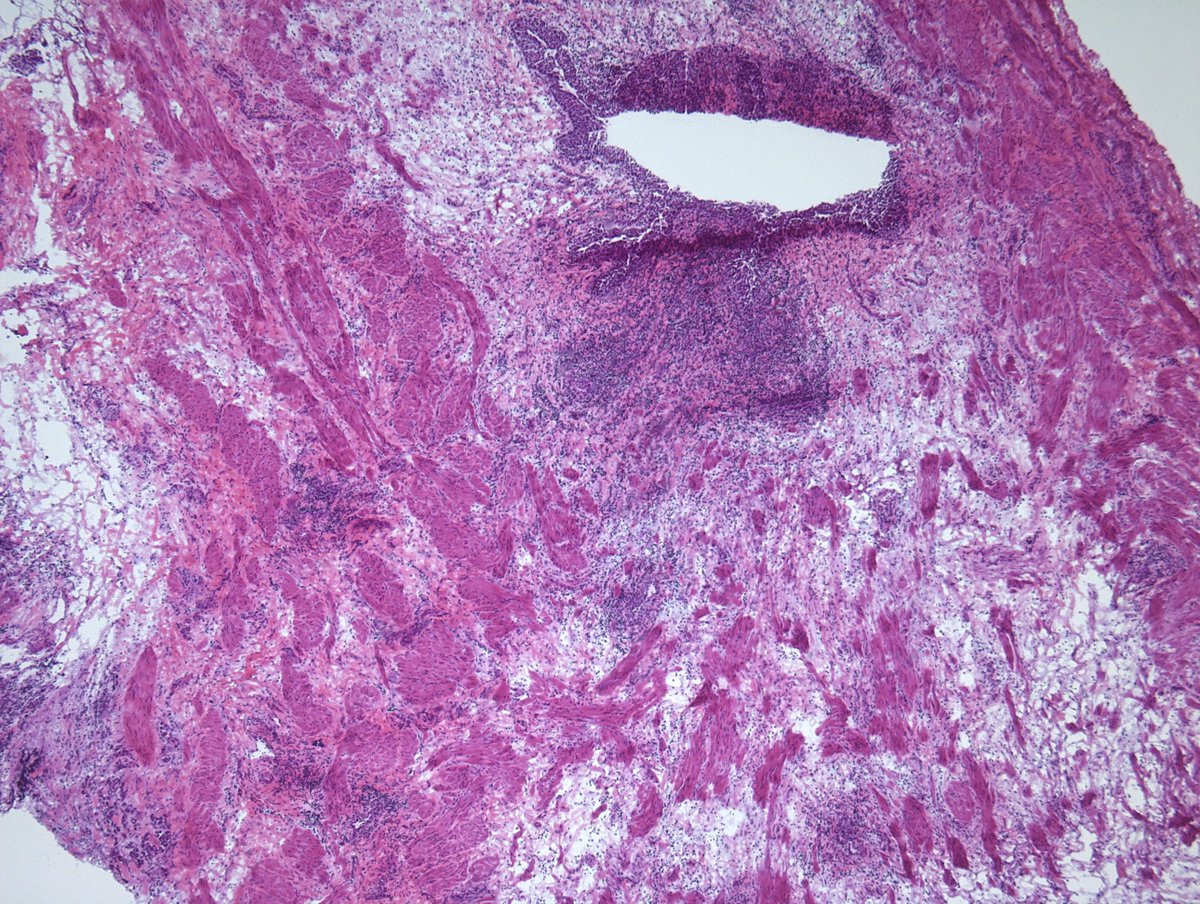

🔥A TIP for diagnosing MALT Lymphoma starts with low magnification.

🎯I search for the muscularis mucosa and see it at the highest magnification.

👉Physiologic lymphoid collection typically does not infiltrate the muscularis mucosa.

Here is a gastric MALT Lymphoma.

#gipath